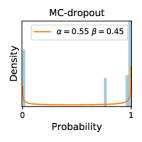

5.1 Distribution of Uncertainty Scores

In contrast, the MC-dropout method showed the worst overall performance among the three, as it can be seen from the high ratios of SL0 examples among the uncertain negatives in Figure 4. The histograms in Figure 2 provides another perspective to look into the phenomenon, where a decent proportion of MC-dropout model’s predictions on SL0 inputs entailed low confidence (far from 0 or 1), which from another angle explained why MC-dropout was less specific in terms of lower FNP; many no-DR inputs (i.e. SL0) were erroneously assigned high uncertainty by MC-dropout models.

It is still an open question why the evaluated MC-dropout networks signaled relatively high uncertainty on SL0 & SL3 & SL4 data that are less likely to be ambiguous. We conjecture that much of the “uncertainty” indicated by disagreement among test-time dropout samples actually reflects the stochastic nature of dropout networks rather than the real decision uncertainty associated with the data. It is worth noting that the MC-dropout model we evaluated was not weak per se; they all achieved above Area Under Curve (AUC) scores on test sets. The weakness of individual test-time samples (which explains their low-confidence predictions on SL0 & SL3 & SL4) might have been hidden when they are aggregated into an ensemble—a well-known advantage of ensemble learning. Our results suggested that the uncertainty information given by implicit ensemble methods such as MC-dropout and TTA might not be as reliable as that from explicit ensemble approaches (e.g., stacking ensembles). Similar findings on MC-dropout can be found in some previous papers [1].